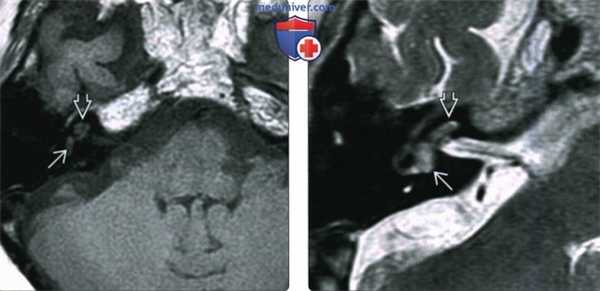

(Слева) При аксиальной МРТ Т1 ВИ С+ FS у годовалого мальчика с перенесенным менингитом и нейросенсорной тугоухостью определяется патологическое контрастирование базального завитка улитки с обеих сторон, сопоставимое с менингогенным лабиринтитом.

(Справа) При аксиальной МРТ Т2 ВИ FSE у пациента с двухсторонним лабиринтитом определяется гиперинтенсивная жидкость (норма) в улитке с обеих сторон. Наличие жидкости с типичным или слегка гипоинтенсивным сигналом позволяет отличить лабиринтит от объемного образования.

(Слева) При аксиальной МРТ Т1 ВИ С+ у пациента с внезапно возникшим головокружением и тугоухостью на фоне вирусного лабиринтита определяется патологическое контрастное усиление завитков улитки и преддверия.

(Справа) При аксиальной МРТ Т1 ВИ С+ определяется контрастирование улитки и внутреннего слухового канала у пациента с двухсторонним отомастоидитом, оталгией, параличом ЧН VII и тугоухостью. Барабанный сегмент ЧН VII в этом примере тимпаногенного лабиринтита также утолщен и накапливает контраст.